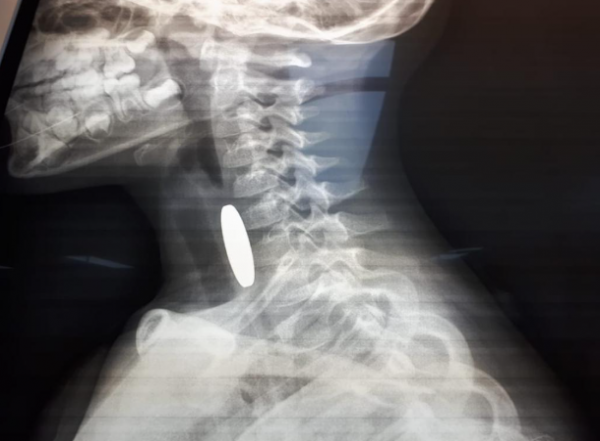

وكالة الناس – أنقذت مرتبات دورية نجدة تابعة لشرطة مادبا أثناء الوظيفة الرسمية حياة طفل يبلغ من العمر ثلاثة أعوام ونصف، بعد أن تعرض لحادثة اختناق إثر ابتلاع عملة معدنية في منطقة لواء ذيبان.

وفي التفاصيل، قال والد الطفل محمد الجديعات لإذاعة الأمن العام، إنه وبعد أن لاحظ أن طفله يجد صعوبة بالتنفس قام بشكل فوري بإسعافه باتجاه مستشفى الأميرة سلمى الحكومي، حيث صادف وجود دورية نجدة على مقربة من منزله وعلى الفور استنجد بهم، ليقوم أفراد الدورية بتقديم الإسعافات الأولية اللازمة باحترافية لمثل هذه الحالات بعد أن ابلغهم أنه قد ابتلع قطعه معدنية .